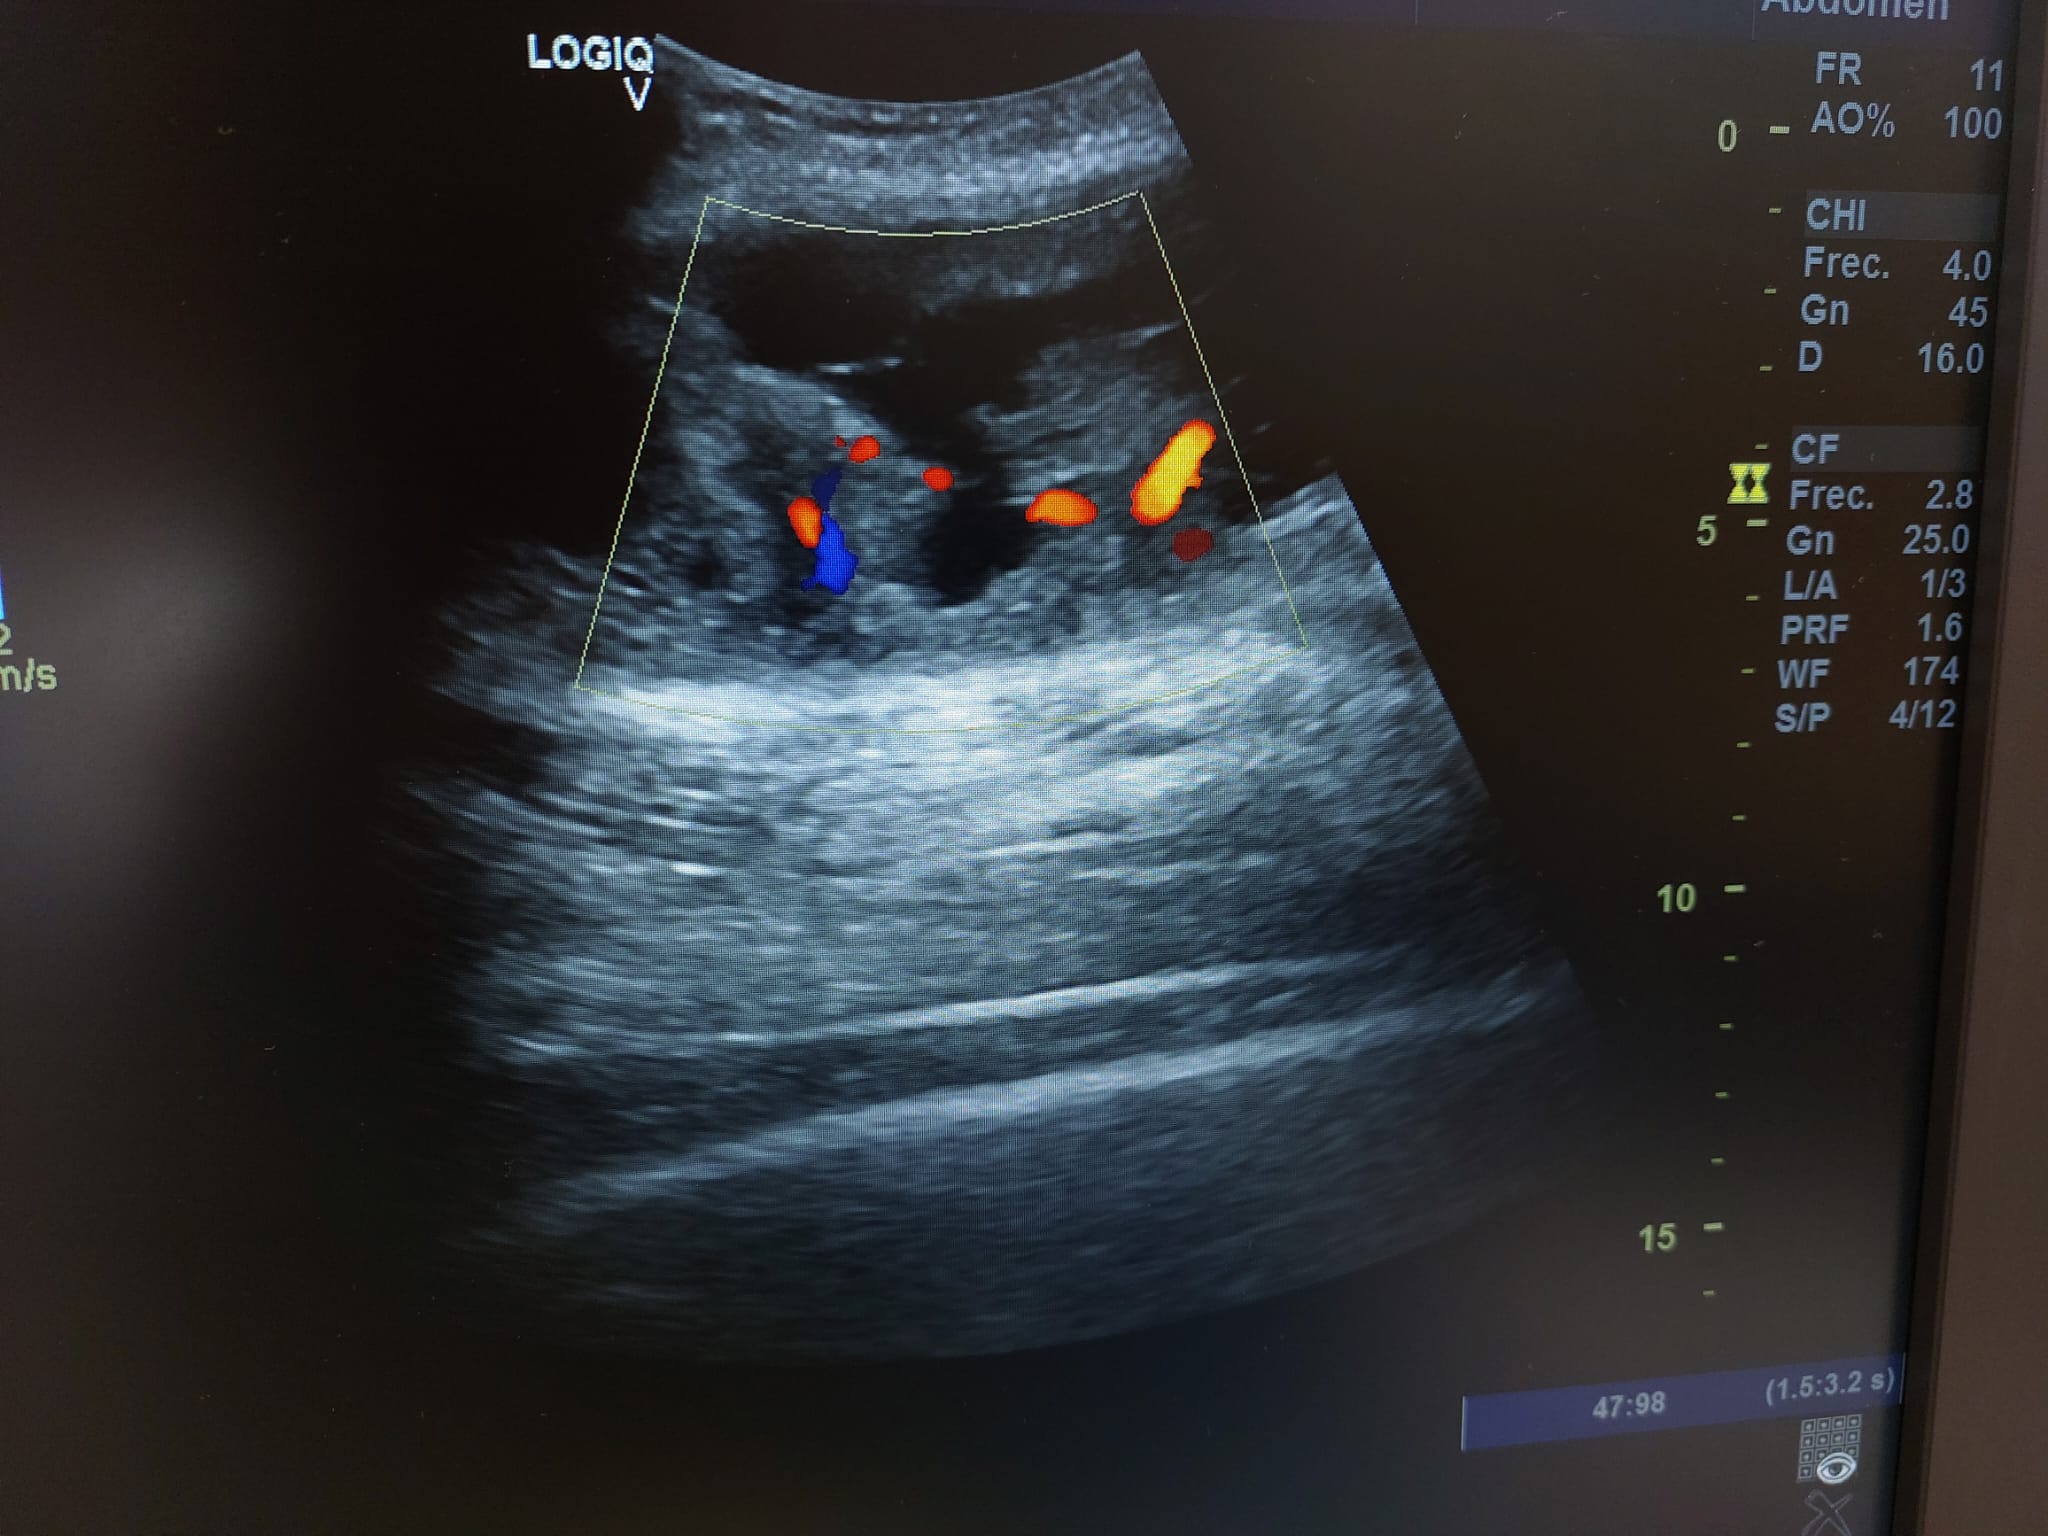

Descripción de los hallazgos ecográficos y las imágenes más relevantes para la resolución del caso

Se realiza ecografía observando colección anecoica a nivel muscular compatible con hematoma organizado, de aproximadamente 7 x 4 cm.

En el seguimiento se observa evolución tórpida sin mejoría clínica y en la ecografía de control se observa aumento notable de tamaño respecto al previo, estructura heterogénea de imagen anecoica con septos internos. Se aprecia edema intramuscular perilesional y captación al activar el Doppler. Se plantea la posibilidad de un hematoma sobreinfectado o, debido a su importante crecimiento, una probable etiología neoplásica. Tras hallazgos descritos en consulta, COT solicita de forma urgente la realización de RNM y biopsia de la lesión. Posteriormente, el resultado de las pruebas complementarias confirman diagnóstico de sarcoma histiocítico.